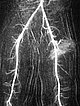

Weitere selektive Partikelembolisation. Die mit Kontrastmittel gemischten Embolisationspartikel verbleiben in den Tumorgefäßen.

Auch in der Übersichtsangiographie über die linke Arteria iliaca externa zeigt sich keinerlei Perfusion des Tumors mehr, die Tumorvaskularisation ist somit erfolgreich superselektiv vollständig verschlossen. Alle nicht pathologischen Arterien sind erhalten.